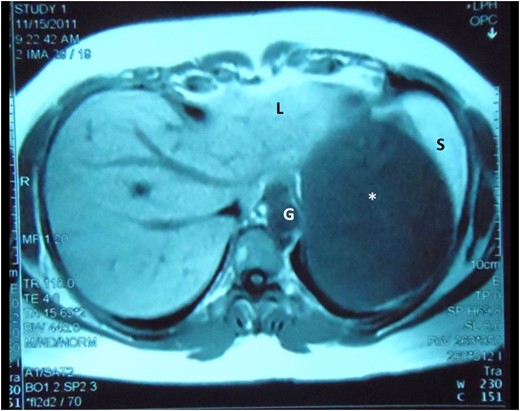

Abdominal MRI demonstrates the cyst (asterisk) intimately related to the left lobe of liver (L), spleen (S) and gastric body (G), still without a clearly demonstrable plane between the structures.